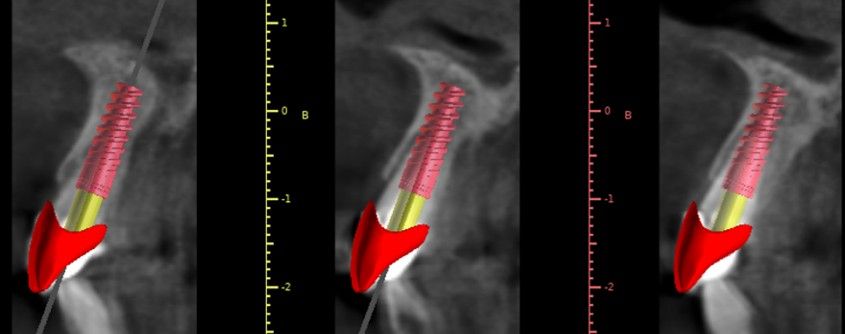

Una vez completado el análisis clínico y radiológico, se llevó a cabo un encerado diagnóstico digital con el objetivo de planificar previamente tanto el tipo de implante como el pilar protésico más adecuado para la restauración inmediata (Figura 2). A partir de dicho encerado, se confeccionó una corona provisional tipo “cáscara de huevo”, destinada a ser rebasada de manera directa en clínica tras la colocación del implante.